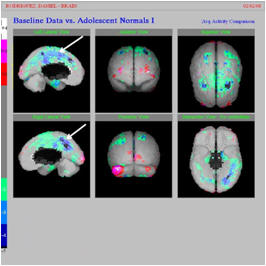

Imagen de un Brain SPECT scan demuestra la disminución de la función en los lóbulos temporales y frontales causada por la activación microglial.

Es bien reconocido por expertos que los lóbulos temporales y frontales no trabajan correctamente en niños con autismo debido a la activación microglial.

Muchos de los síntomas del autismo pueden ser explicados claramente por disfunción en los lóbulos temporales y frontales y en otras partes del cerebro.